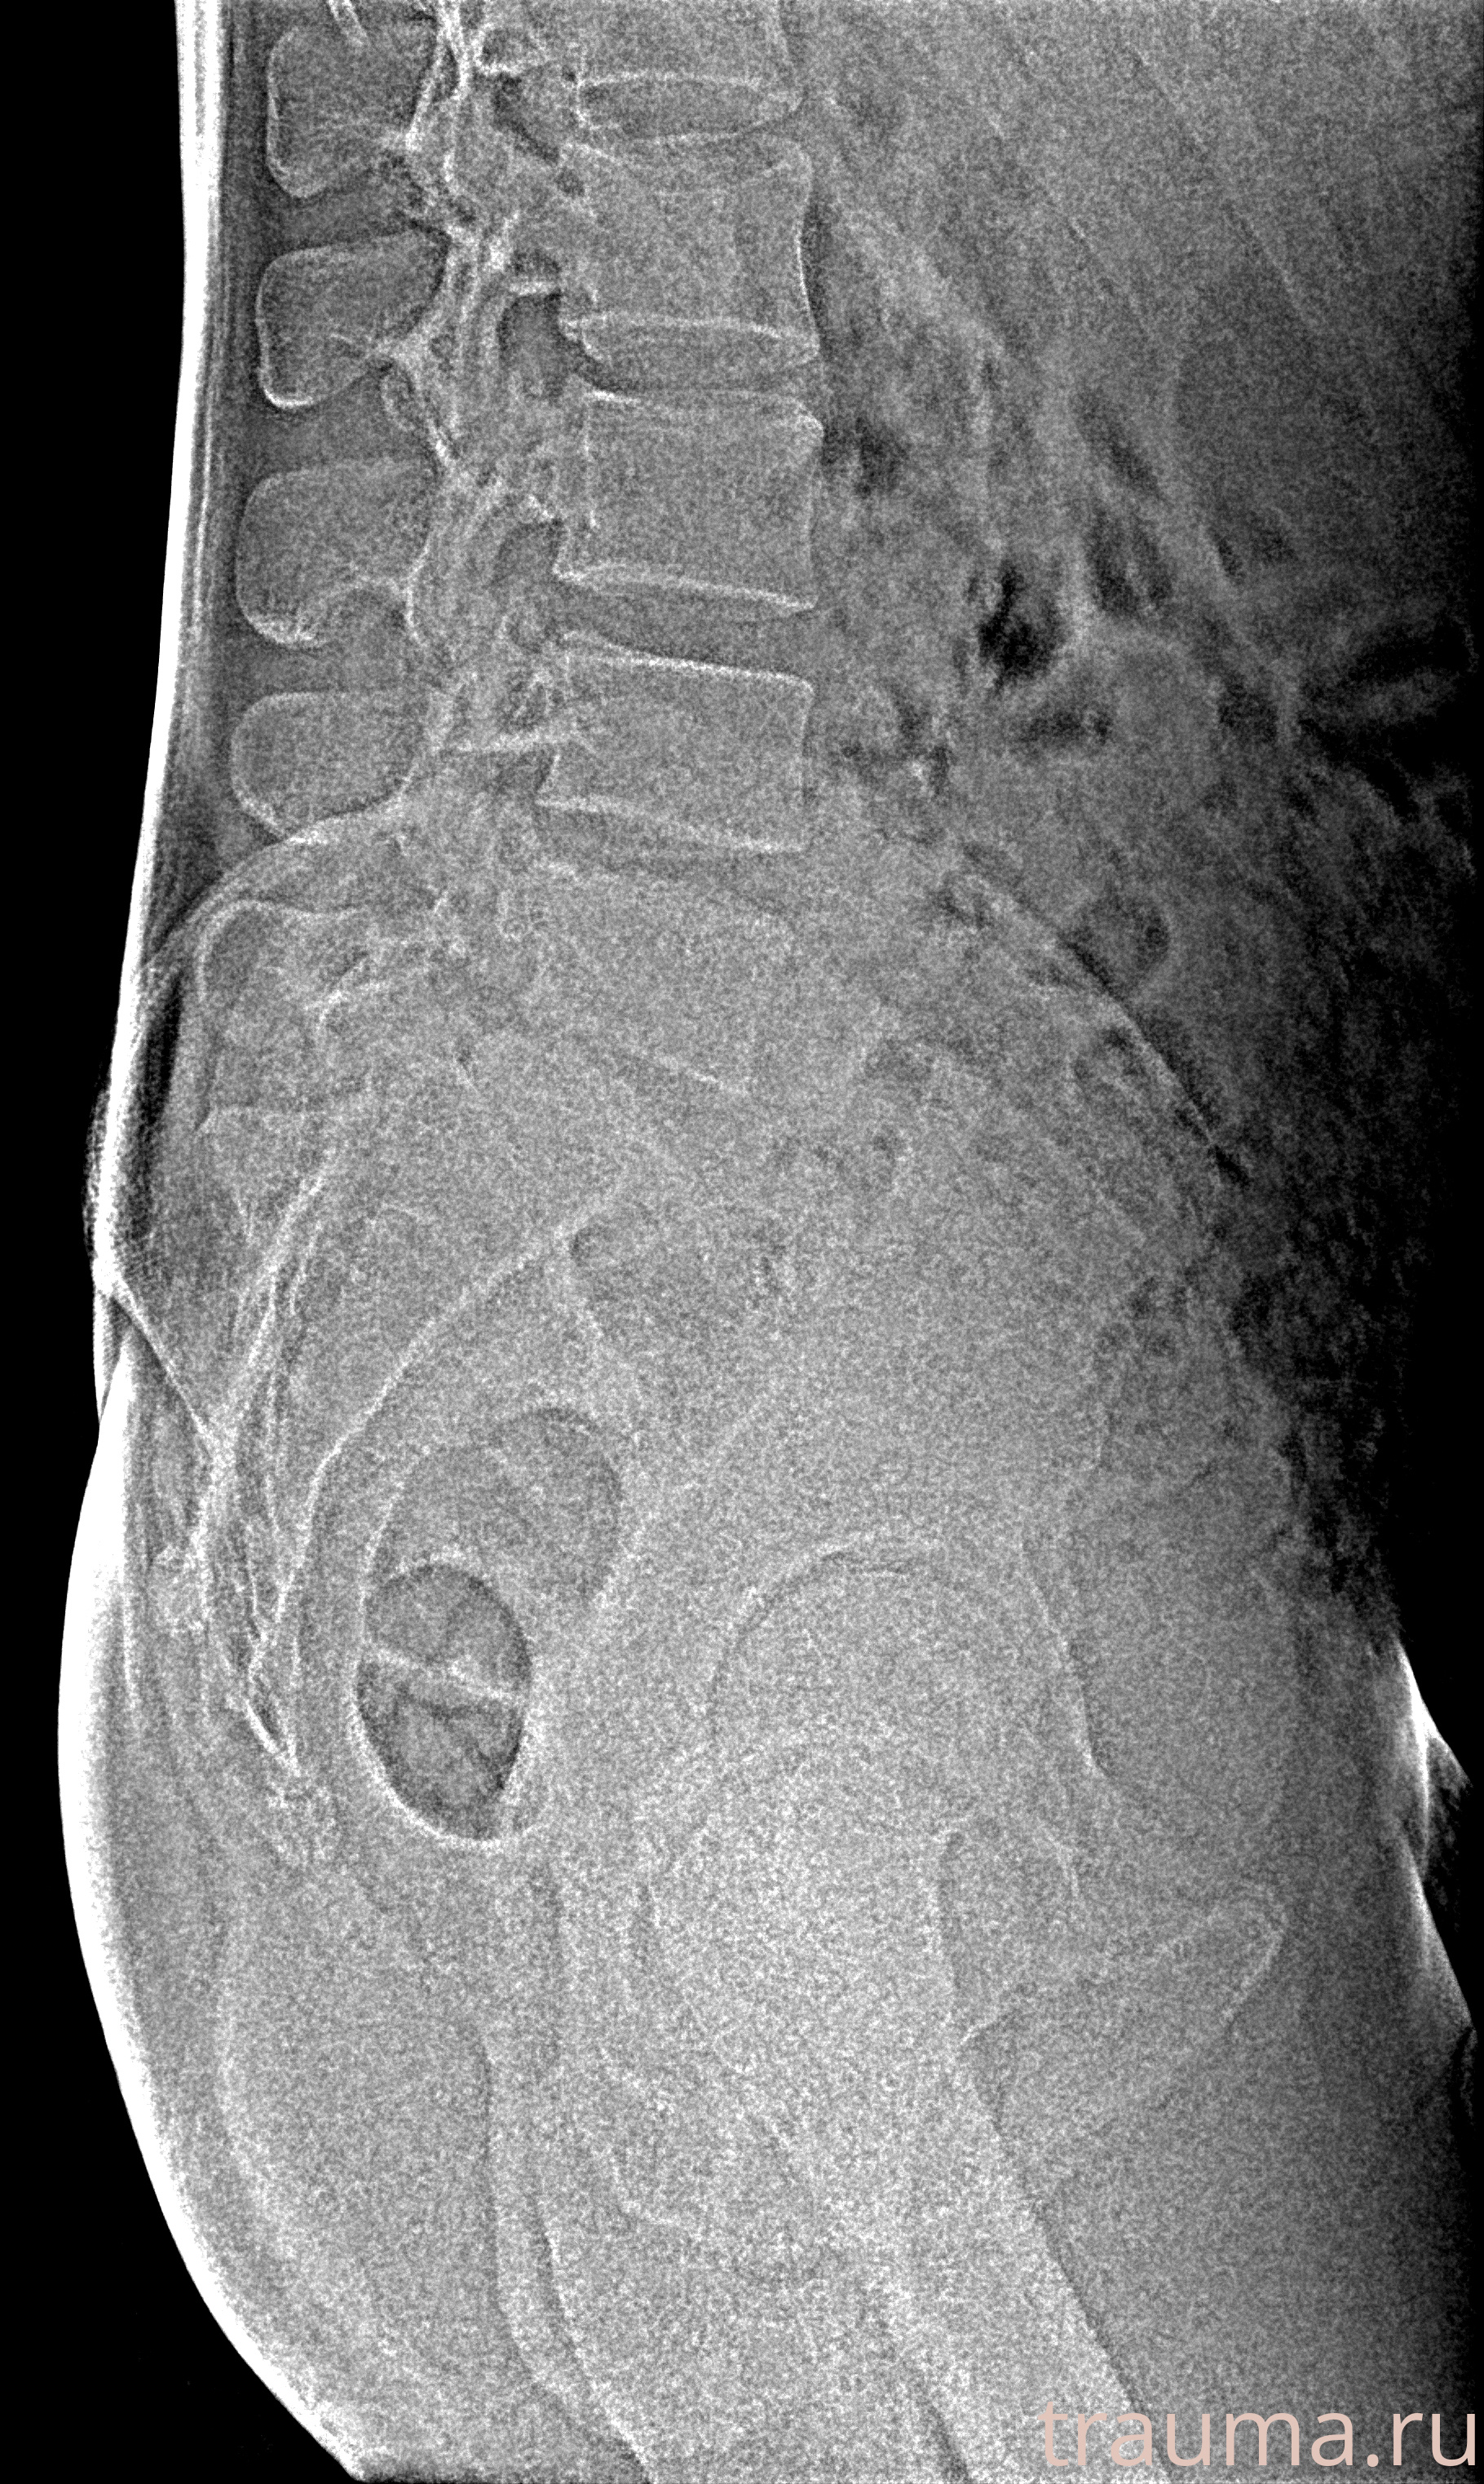

Рентгенограммы

Рентген на дому: по вашему адресу приезжает врач-рентгенолог, травматолог-ортопед с мобильным рентгеновским аппаратом, проводит диагностику травмы или заболевания, делает необходимые рентгенограммы, дает рекомендации по дальнейшему лечению. Получить качественные снимки в домашних условиях возможно благодаря уникальной методике, разработанной МосРентген Центром для института  Склифосовского